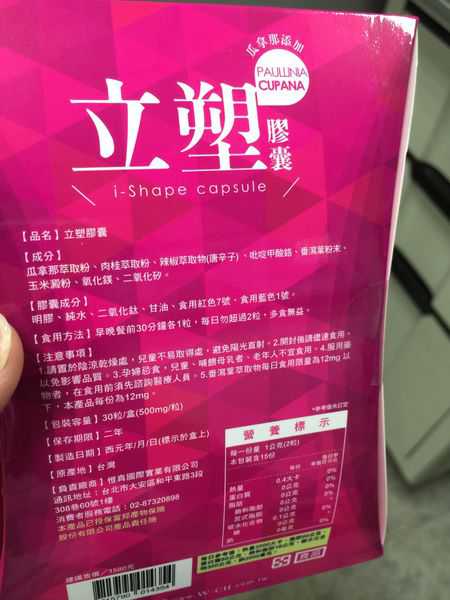

同時,謝謝【女人知己試用大隊】提供的–Supercut塑魔纖立塑膠囊

好啦,廢話不多說,就來試試繽紛小桃紅--Supercut塑魔纖立塑膠囊

每一盒Supercut塑魔纖立塑膠囊都有三小包,每一小包有10顆膠囊

Supercut塑魔纖立塑膠囊的成分有:瓜拿那萃取粉、肉桂萃取粉、辣椒萃取物(唐辛子)、吡啶甲酸鉻、番瀉葉粉末、玉米澱粉、氧化鎂、二氧化矽。

之前上過相關課程,成分表是依照每項成分的多寡來排列順序,排在最前面的就是產品的主要成分!

那我就跟大家分享瓜拿那萃取粉、肉桂萃取粉和辣椒萃取物吧

瓜拿那萃取和辣椒萃取是可以幫助纖體瘦身常見的營養素!

1.「瓜拿那」是原產於亞馬遜流域的一種藤蔓植物,富含酵素可以幫助排便順暢,並且能抑制脂肪分解酵素,此外也有降低食慾的效果喔~~萃取物中含有天然咖啡因,可以提高新陳代謝率以及排出多餘水分!

2.「辣椒萃取物」則是可以幫助體內脂肪燃燒、增加卡路里的消耗,達到防止脂肪積聚的效果

3.「肉桂萃取物」看到肉桂,就想到麥當勞的蘋果派或是手掌麵包,雖然很多人很害怕那味道,但艾哥愛死肉桂了!!!!肉桂在古代被視為是最有價值的東方香料之ㄧ,中世紀時,肉桂的聲望僅次於昂貴的黑胡椒,除了香料和薰香價值, 傳統上肉也被用來治療消化不良、脹氣、關節疼痛、出血和經痛,研究也指出肉桂可以促進新陳代謝喔

食用方式:早晚餐前30分鐘各1粒,每日不超過2粒。(多食無益)

包裝是桃紅色的